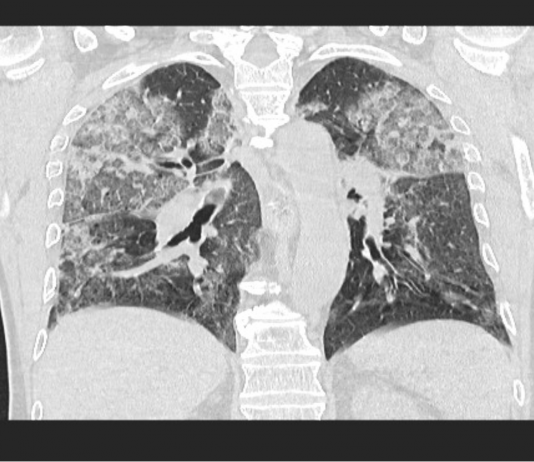

Paziente maschio 75 anni. Anamnesi remota muta, non comorbidità. Esordio con...